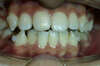

Vues après le Traitement